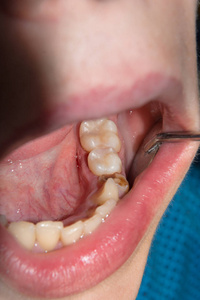

最后一颗后槽牙已经一半都没了有图慎入